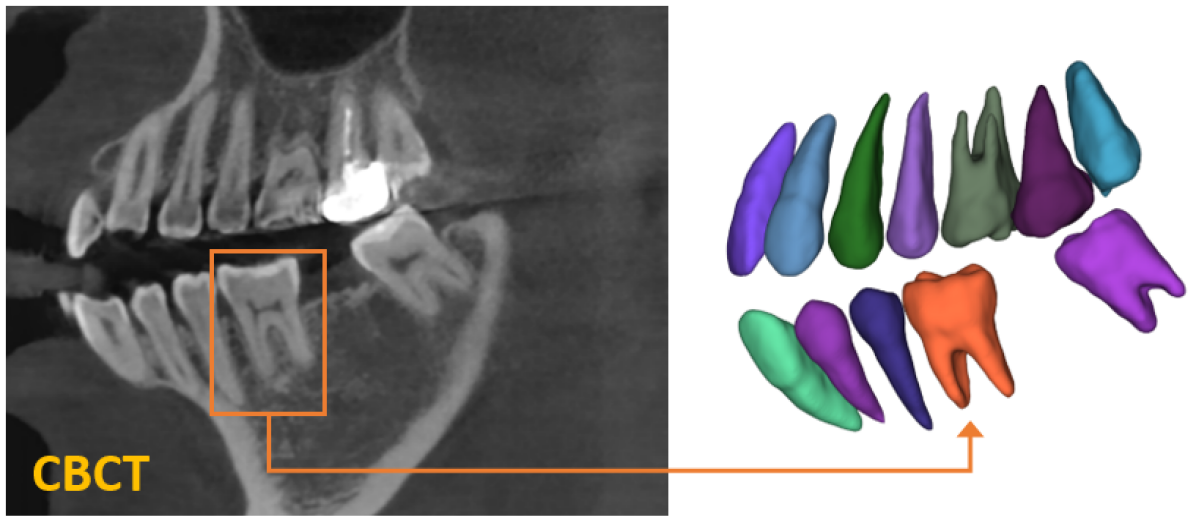

Individual tooth segmentation from cone beam computed tomography (CBCT) images is an essential prerequisite for an anatomical understanding of orthodontic structures in several applications, such as tooth reformation planning and implant guide simulations. However, the presence of severe metal artifacts in CBCT images hinders the accurate segmentation of each individual tooth. In this study, we propose a neural network for pixel-wise labeling to exploit an instance segmentation framework that is robust to metal artifacts. Our method comprises of three steps: 1) image cropping and realignment by pose regressions, 2) metal-robust individual tooth detection, and 3) segmentation. We first extract the alignment information of the patient by pose regression neural networks to attain a volume-of-interest (VOI) region and realign the input image, which reduces the inter-overlapping area between tooth bounding boxes. Then, individual tooth regions are localized within a VOI realigned image using a convolutional detector. We improved the accuracy of the detector by employing non-maximum suppression and multiclass classification metrics in the region proposal network. Finally, we apply a convolutional neural network (CNN) to perform individual tooth segmentation by converting the pixel-wise labeling task to a distance regression task. Metal-intensive image augmentation is also employed for a robust segmentation of metal artifacts. The result shows that our proposed method outperforms other state-of-the-art methods, especially for teeth with metal artifacts. Our method demonstrated 5.68% and 30.30% better accuracy in the F1 score and aggregated Jaccard index, respectively, when compared to the best performing state-of-the-art algorithms. The primary significance of the proposed method is two-fold: 1) an introduction of pose-aware VOI realignment followed by a robust tooth detection and 2) a metal-robust CNN framework for accurate tooth segmentation.

Digitized orthodontic applications in dentistry have increased based on the development of cone beam computed tomography (CBCT) imaging. CBCT is a widely used medical imaging technique that provides high resolution 3D volumetric data. To build an effective computer-aided diagnosis system in orthodontic applications, such as oral treatment planning for tooth reformation and implant guide simulation, automatic segmentation of individual teeth from the CBCT images is an essential prerequisite (Fig. 1). However, accurate segmentation of an individual tooth from a CBCT image is a challenging task owing to heterogeneous intensity distribution, unclear boundaries between the tooth root and alveolar bone (Fig. 2a), and diverse shapes and poses. Moreover, the majority of CBCT images contain severe metal artifacts that hinder the accurate segmentation of teeth (Fig. 2b). In this study, we propose a fully automated instance segmentation framework using 3D images of teeth that is robust to several challenging conditions of the teeth, such as, dynamic poses, missing teeth, inter-tooth proximity, and presence of severe metal artifacts.

In this study, we propose a fully automatic, hierarchical method that performs accurate individual tooth detection followed by a CNN based on single pixel-wise labeling to segment the tooth (Fig. 3). We first extracted the volume-of-interest (VOI) region by pose regression using neural networks. Then, the extracted VOI region was realigned based on the pose (i.e., axes). Subsequently, we detected individual teeth and performed individual tooth segmentation. The key components of our method are the accurate tooth detection framework through VOI realignment, which reduces the inter-overlapping area between boxes, multiclass classification within a detector, which boosts the accuracy of metal-tooth detection, and the metal-robust CNN for accurate tooth segmentation.